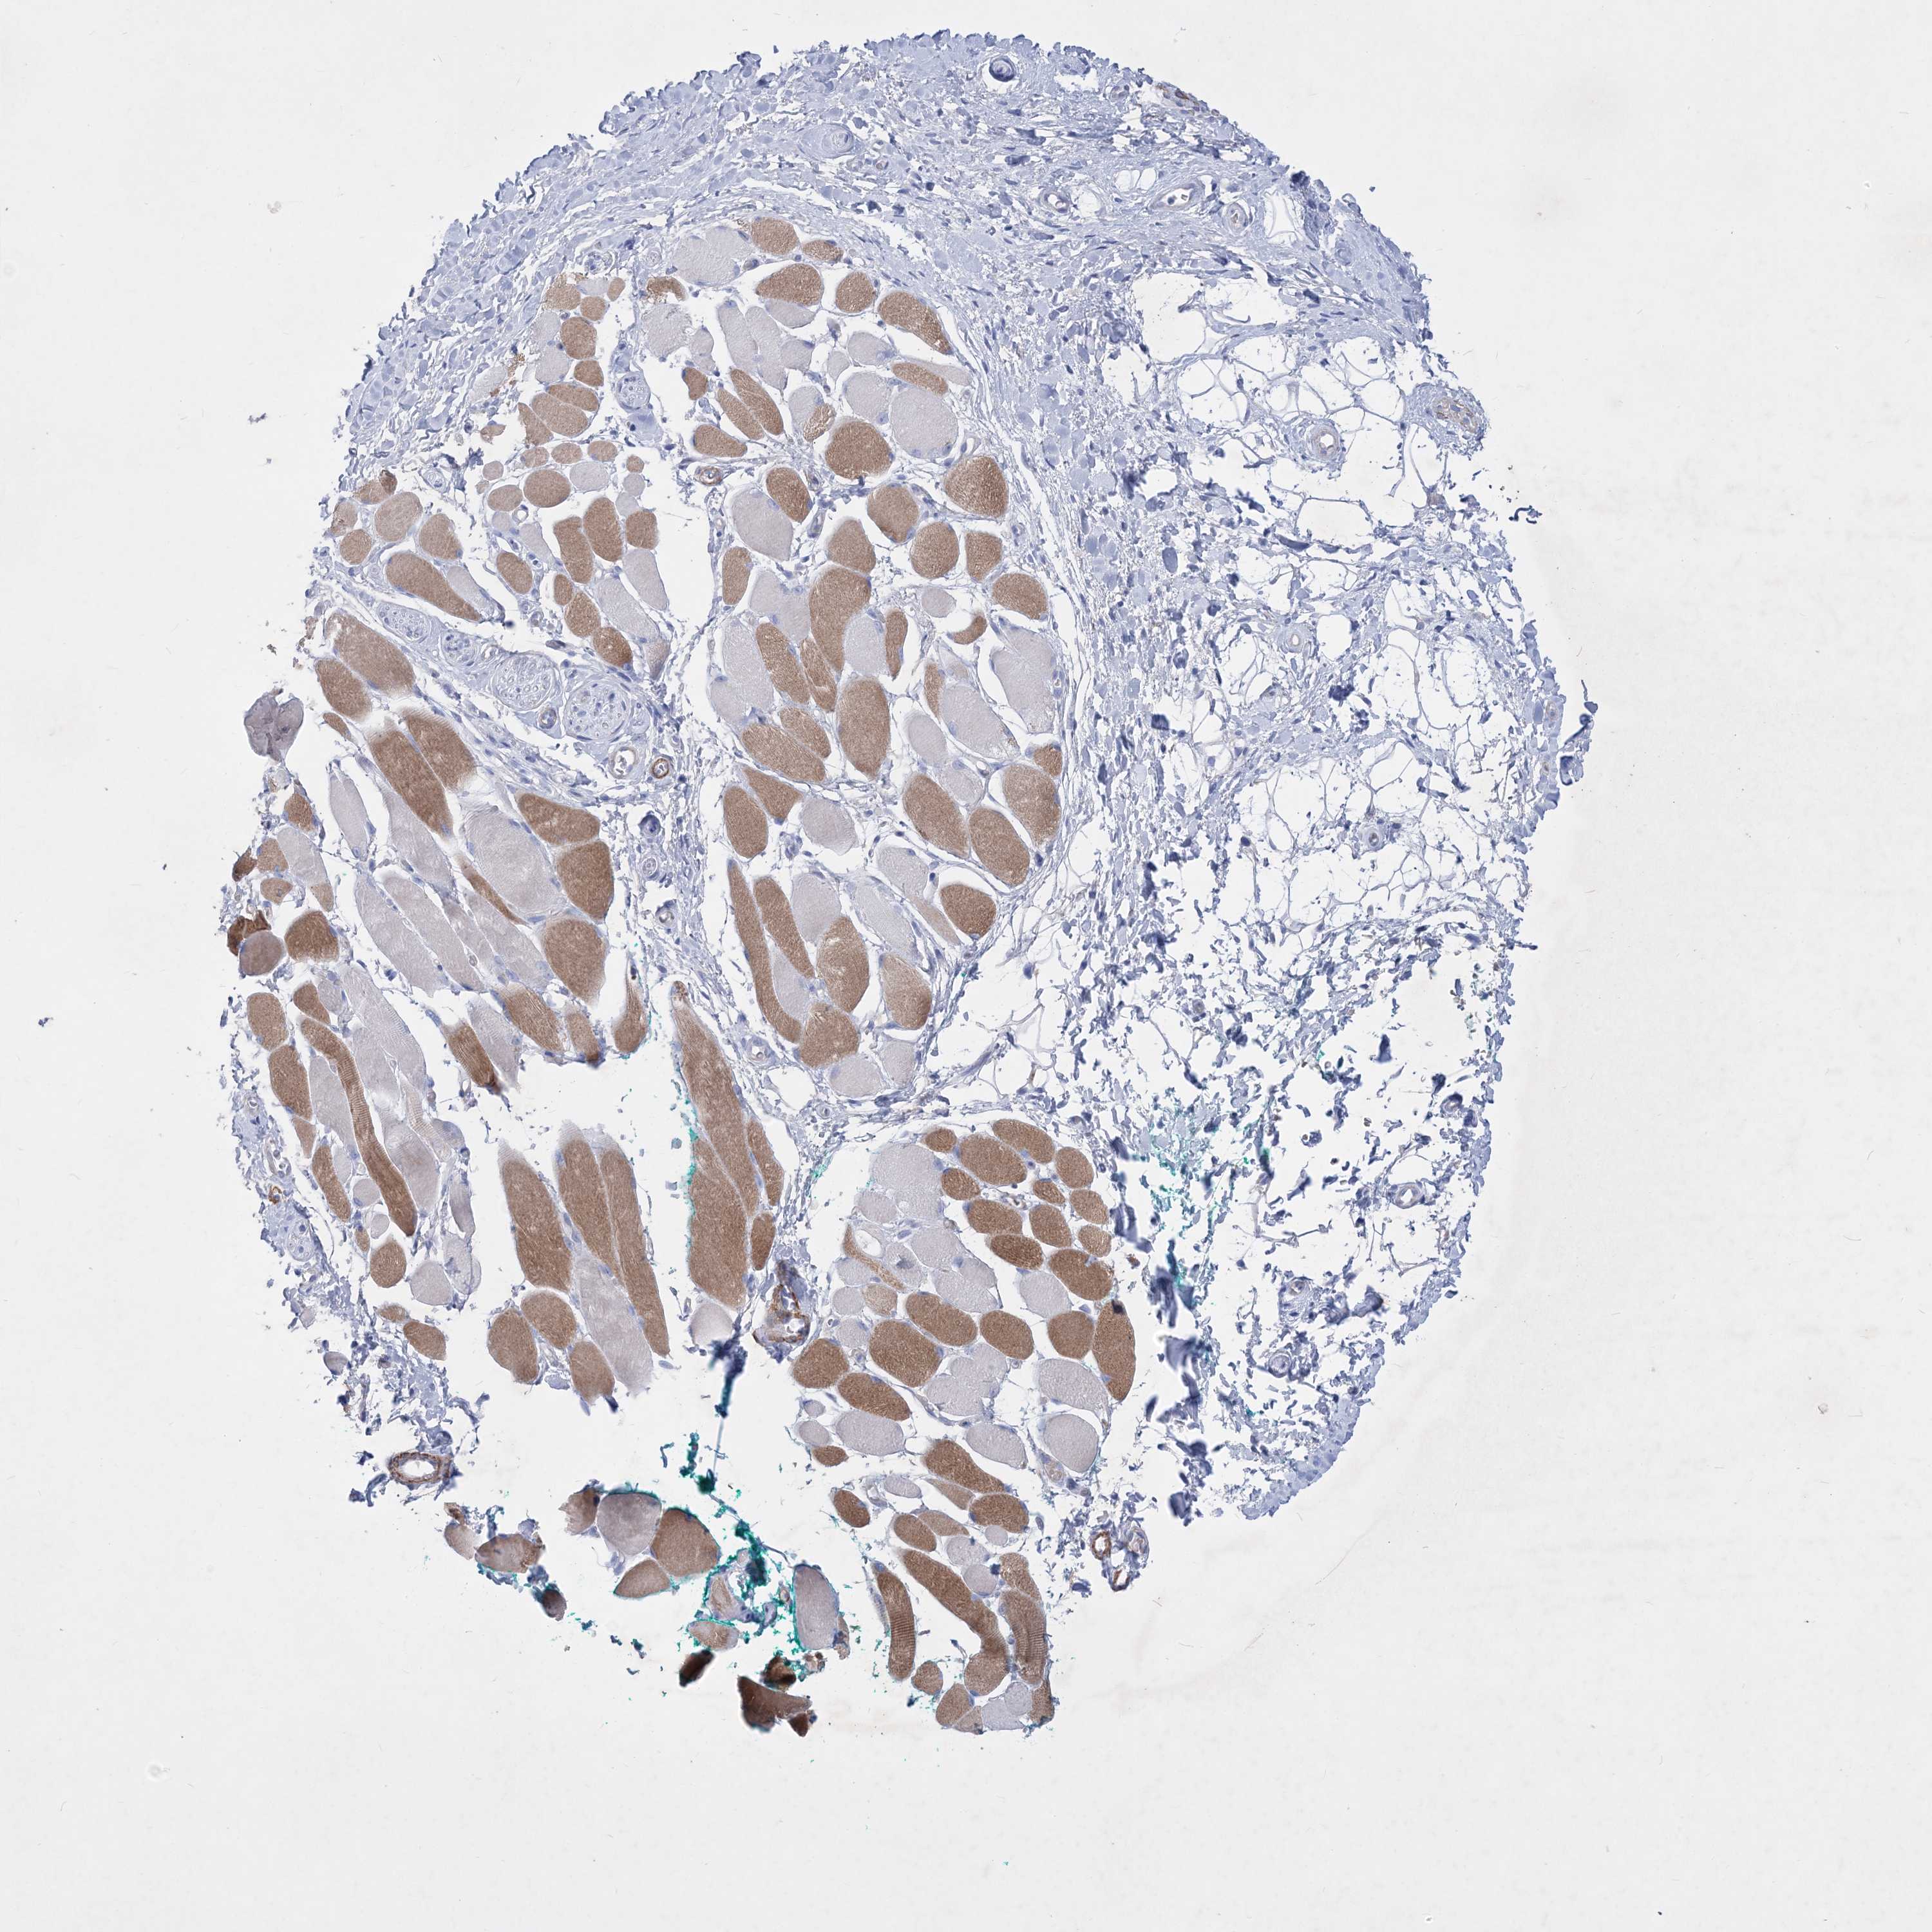

Basal cell and squamous cell cancer

SKIN CANCER - Protein expressioni

A mouse-over function shows sample information and annotation data. Click on an image to view it in a full screen mode. Samples can be filtered based on level of antibody staining by selecting one or several of the following categories: high, medium, low and not detected. The assay and annotation is described here.

Antibody stainingi

Antibody staining in the annotated cell types in the current human tissue is reported as not detected, low, medium, or high, based on conventional immunohistochemistry profiling in selected tissues. This score is based on the combination of the staining intensity and fraction of stained cells.

Each image is clickable and will lead to virtual microscopy that enables deeper exploration of all samples and also displays staining intensity scores, fraction scores and subcellular localization as well as patient and tissue information for each sample.

Antibody HPA037795

Antibody HPA038419

Staining

High

Medium

Low

Not detected

Intensity

Strong

Moderate

Weak

Negative

Quantity

>75%

75%-25%

<25%

None

Location

Nuclear

Cytoplasmic/membranous

Cytoplasmic/membranous,nuclear

Basal cell carcinoma

Squamous cell carcinoma, NOS

Squamous cell carcinoma, metastatic, NOS